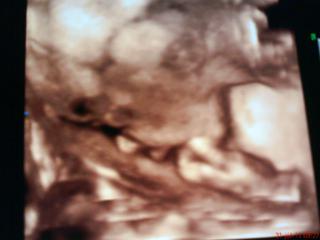

ahoj baby.tak vysledky dosli az teraz.a recept budem mat az v pondelok. mam nejaku pliesnovu mykozu a ta vraj mohla sposobit aj unik poldovej vody.vraj je to normalne.tak v pondelok recept a hajde na ATB.dufam ze to malemu neuskodi. a ozaj v pondelok idem na 4 D zase do pruskeho 😉 mangel do mna hucal ze to chce vidiet ze somnou este nebol na sone a ze si to zaplati tak hovorim preco nie.tesim sa aspon zase uvidim drobca a dozviem sa miery a podobne. dnes som nakupila vecicky dalsie tak vsetko perem.idem dat fotak do nabijacky a pofotim vsetko 😉

No,vcera som mala poradnu 🙂Vdaka hnusnemu pocasiu bola prazdna cakaren a lekar sa mi mohol venovat.Urobil mi utz [hoci nemusel]a Simonku sme celu skontrolovali 😉Krasne rastie,v 24tt vazi 625g 😉

Celu dobu pocas utz bola otocena chrbtom a zadkom,no nakoniec sa zlutovala nad maminkou,na okamih sa otocila a lekarovi sa podarilo ,,cvaknut,, ju z profilu ako si cucka prsteky....